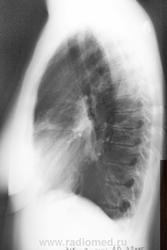

Осумкованный плеврит? в заднем отделе левого синуса.Так ли это?

Собираюсь на консультацию к кардиологу и сегодня сделала рентген в 2 проекциях. И Врач-ренгинолог меня просто ошарашил дословно: Осумкованный плеврит? в заднем отделе левого синуса.

Однозначно, что именно "осумкованного плеврита", в данном случае нет. Однако архивчик есть, да и верхушечки внимания требуют.

Вероятно левосторонняя пневмония в 3-м сегменте.

Здрасти . У вас по снимкам легочный рисунок резко усилен с обоих сторон , справа корень расширен и деформирован .Слева в синусе похоже небольшое количество жидкости ,но насчет осумкованности я сильно сомневаюсь . Вы анализы сдавали ? СОЭ, лейкоциты ..... Верхушки чистые , но вот справа корень и легочный рисунок мне не нравтся , да и что может вызвать выпот в плевральную полость . Было бы хорошо если бы вы сделали манту